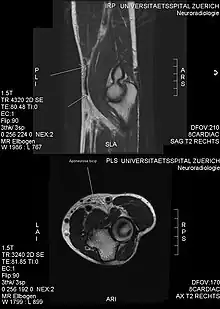

MRI: tear of the distal biceps tendon

Injuries can occur due to incorrect form, careless mistakes, or "ego lifting". The most common injury caused by bicep curls is a tear of the biceps tendon.[20] There are two main causes of biceps tendon tears: excessive weight and overuse. Ego lifting is an attempt to lift weights that are heavier than the weightlifter's capability.[21] During ego lifting, the lifter's form will be twisted because the weight is too heavy, and if the weight is far beyond the lifter's strength, then there is a likelihood to suffer from biceps tears.[22]